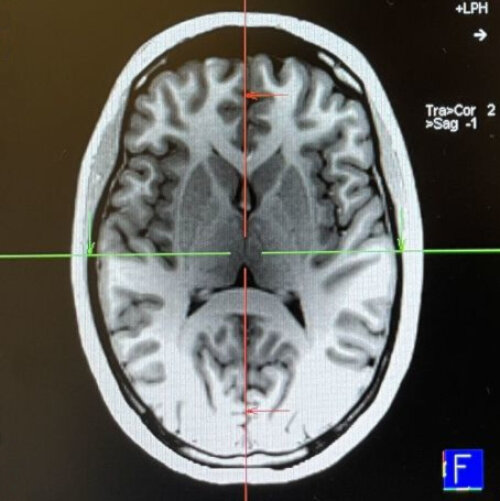

Map users process information from the legend more efficiently when it is placed on the right side of the map. The reason for this lies in the brain.